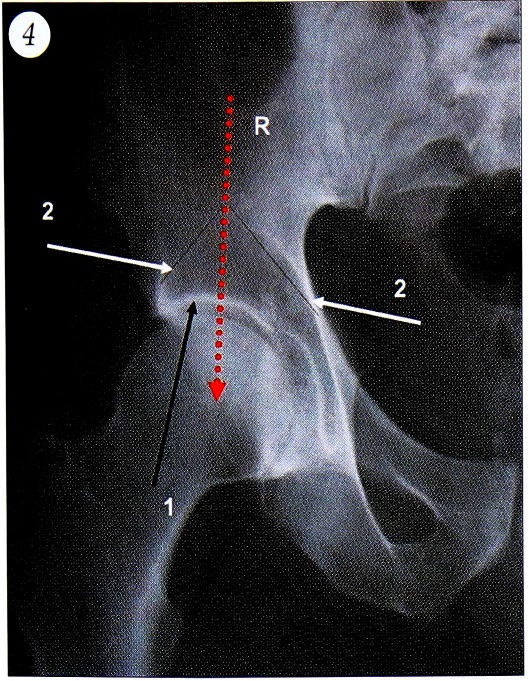

Согласно закону Вольфа, архитектоника кости определяется направлением линий наибольших напряжений. Следовательно, направление костных балок конкретного сегмента кости определяется направлением векторов сил, действующих на этот сегмент. Поэтому, анализируя архитектонику кости в области тазобедренного сустава по рентгенограммам, выполненным в переднезадней проекции, мы можем судить о направлении векторов и балансе сил, действующих на него. В области тазобедренного сустава костные балки формируют следующие структуры (рис. 4): сурсил — нагружаемую поверхность плотной структуры в области крыши вертлужной впадины; «готическую арку» — два пучка костных балок, поддерживающих сурсил. Первый пучок начинается от наружного края крыши вертлужной впадины и имеет краниомедиальное направление. Этот пучок формируется под действием суммарного вектора сил отводящих мышц бедра. Второй пучок начинается от lamina quadrilaterum, имеет краниолатеральное направление и формируется под действием суммарного вектора сил m. iliopsoas. Пересечение этих пучков формирует фигуру «готической арки». Вектор результирующей силы, действующей на тазобедренный сустав, проходит через верхушку «готической арки» к центру ротации головки бедренной кости и делит сурсил пополам. В литературе нет единого мнения о направлении результирующей силы в нормальных биомеханических условиях. Pauwels [14] считал, что ее вектор должен иметь краниомедиальное отклонение от вертикальной оси таза в 16° для обеспечения баланса сил. По данным Clark и Науnor [12], Pedersen и соавт. [15], отклонение вектора результирующей силы от вертикальной оси может варьировать от 1° в латеральную сторону до 7° в медиальную. Bombelli [10] полагает, что баланс мышц возможен только тогда, когда вектор результирующей силы проходит строго вертикально.

Рис. 4. Сурсил — нагружаемая поверхность (1), пучки костных балок, формирующие «готическую арку» (2), положение вектора результирующей силы (R).